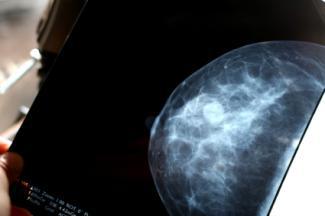

ការពិត៖ មានតែភាគរយតួចបណ្ណោះដែលដុំសុដន់ក្លាយទៅជាជំងឺមហារីក។ ប៉ុន្តែប្រសិនបើអ្នករកឃើញដុំពករឹងក្នុងសុដន់របស់អ្នក ឬសម្គាល់ឃើញថាមានការផ្លាស់ប្តូរជាលិកាសុដន់ អ្នកមិនគួរព្រងើយកន្តើយឡើយ។ វាជាការសំខាន់ណាស់ដែលអ្នកត្រូវទៅជួបគ្រូពេទ្យដើម្បីពិនិត្យសុដន់។ គ្រូពេទ្យអាចធ្វើការថតសុដន់ ដើម្បីកំណត់ថាតើដុំនោះជាដុំដែលគួរឱ្យព្រួយបារម្ភ ឬអត់។

ត្រូវគ្រប់គ្រងសុខភាពរបស់អ្នកដោយការពិនិត្យសុដន់ដោយខ្លួនឯងជាប្រចាំ រក្សាទំនាក់ទំនងជាប្រចាំជាមួយគ្រូពេទ្យរបស់អ្នក ធ្វើការពិនិត្យសុដន់មួយឆ្នាំម្ដង និងកំណត់ពេលនៃការថតកាំរស្មីដើម្បីពិនិត្យរកជំងឺមហារីករបស់អ្នកឱ្យទៀងទាត់។

ការពិត៖ ការថតកាំរស្មីមិនអាចការពារជំងឺមហារីកសុដន់បានទេ ប៉ុន្តែវាអាចសង្គ្រោះជីវិតបានដោយការរកឃើញមហារីកសុដន់ឱ្យបានលឿនតាមដែលអាចធ្វើបាននៅពេលដែលជំងឺនេះអាចព្យាបាលបាន។

ការពិត៖ ការថតកាំរស្មី ឬកាំរស្មីអ៊ិចត្រង់សុដន់ បច្ចុប្បន្នគឺជាស្តង់ដារដ៏ប្រសើរសម្រាប់ការរកឱ្យឃើញជំងឺមហារីកសុដន់ដំណាក់កាលដំបូង។ ការសង្កត់សុដន់នៅពេលធ្វើការថតកាំរស្មីមិនអាចបណ្តាលឱ្យមហារីករីករាលដាលនោះទេ។ យោងតាមវិទ្យាស្ថានជាតិជំងឺមហារីក””ទោះបីការថតកាំរស្មីមានអត្ថប្រយោជន៍ក៏ដោយ វាមានផលប៉ះពាល់ខ្លាំងជាងការប៉ះពាល់នឹងវិទ្យុសកម្មទៅទៀត។””ការថតកាំរស្មីទាមទារឱ្យមានការប្រើប្រាស់កម្រិតវិទ្យុសកម្មតិចបំផុត។ ហានិភ័យនៃគ្រោះថ្នាក់ពីការប៉ះពាល់វិទ្យុសកម្មនេះគឺមានកម្រិតទាបបំផុត។

ស្តង់ដារដែលបានណែនាំគឺការថតកាំរស្មីដើម្បីពិនិត្យរកជំងឺមហារីកមួយឆ្នាំម្ដងសម្រាប់ស្ត្រីចាប់ពីអាយុ ៤០ ឆ្នាំ។ ផ្អែកតាមការសម្រេចចិត្តរបស់អ្នកលើការណែនាំរបស់គ្រូពេទ្យ ហើយត្រូវប្រាកដក្នុងការពិភាក្សាអំពីបញ្ហា ឬការព្រួយបារម្ភណាមួយដែលលោកអ្នកអាចមានជាមួយគ្រូពេទ្យ។